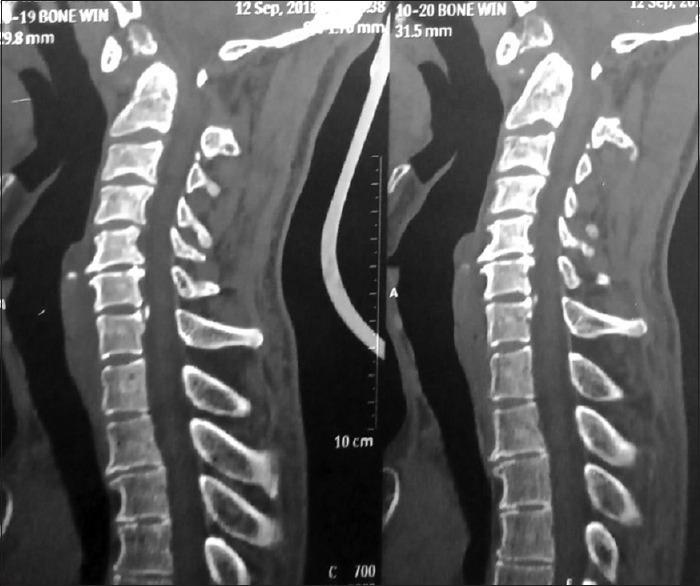

Os odontoideum (OO) was first described by Giacomini in 1886 as separation of the odontoid process from the body of the axis. Instability can consequently occurs at this level due to the failure of the transverse atlantal ligament (TAL) and this atlantoaxial instability can be a cause of progressive neurological deficits. It is considered a rare anomaly of the odontoid process. It is a disease with controversial etiology, debatable incidence, and only a partly known natural history owing to the paucity of the literature on this topic. There are insufficient demographic data about the occurrence of the disease, and most of the management is dictated by the isolated case reports and few studies which have been carried out at handful of institutes. OO is classified into two types by Fielding . based on the anatomic location: orthotopic and dystopic. Orthotopic OO consists of an ossicle that moves with the anterior arch of the atlas, whereas the dystopic type presents as an ossicle near the basion or one that is fused with the clivus. In one magnetic resonance imaging (MRI) study of odontoid morphology, a 0.7% (1 case of 133 patients) incidence was reported. The spectrum of the clinical presentation varies from completely asymptomatic individuals to patients presenting with features of cervical myelopathy. Here, we present a case of 35-year-old-male with dystopic OO who presented to us with features of gradually progressing cervical myelopathy without any obvious history of neck trauma. On investigations, he was found to have atlantoaxial instability with wide atlanto-dens interval. He was treated with the posterior C1-C2 stabilization and reduction of atlantoaxial instability.